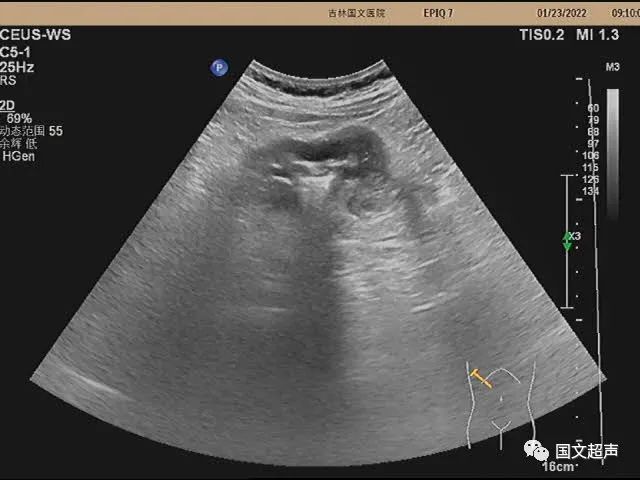

超聲檢查:右側(cè)結(jié)腸肝曲處腸壁不均勻性增厚,走行僵直,蠕動(dòng)不佳,呈“假腎征”,術(shù)后病理:右側(cè)結(jié)腸低分化腺癌。